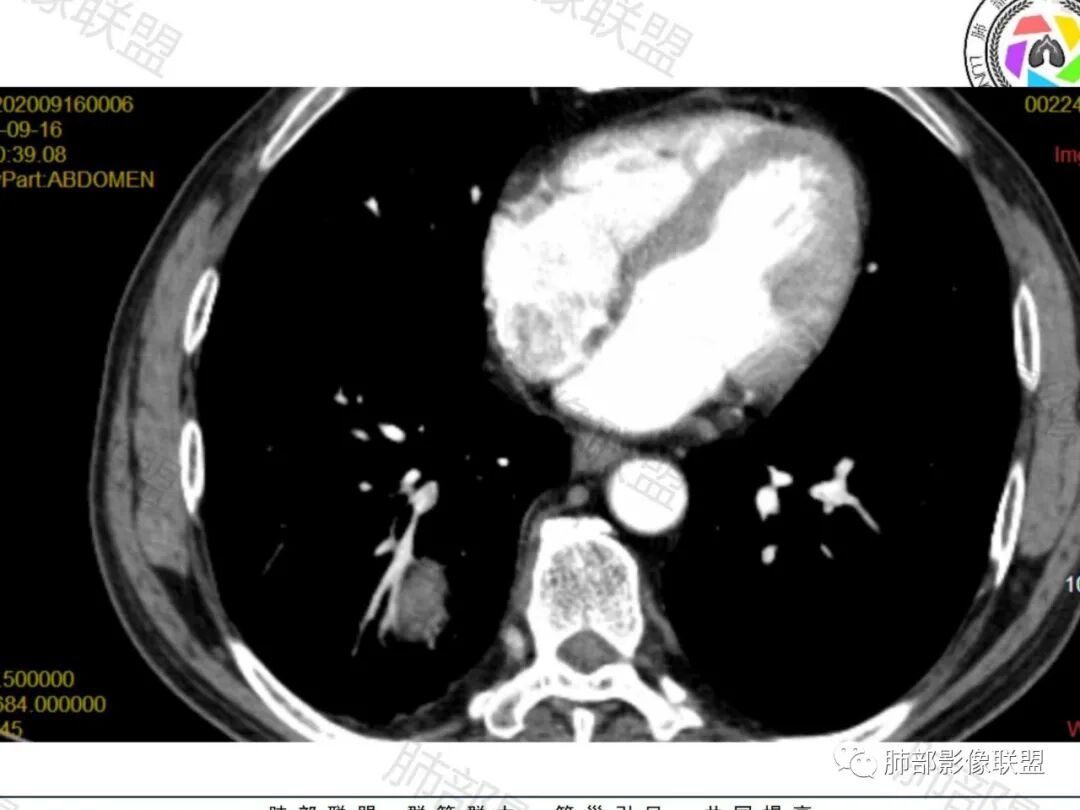

右肺下叶一类圆形肿块影,内缘边缘光滑,外缘边界模糊,可见磨玻璃影,整体以彭隆为主,部分边缘包绕支气管,平扫密度尚均匀,增强后不均匀强化,部分与膈肌黏连,临床,62岁男性,无症状,考虑恶性:腺癌,鳞癌,神经内分泌癌,肉瘤

老年人,偶然发现,右肺下叶类圆形软组织占位,密度较均匀,病灶边缘光滑,无毛刺分叶,支气管血管受挤压向外移位,增强病灶强化较均匀。考虑恶性肿瘤,外向内生长,肉瘤,肉瘤样癌,癌肉瘤,其次神经内分泌癌。

男性,62,胆结石入院胸部CT偶然发现占位。肿标稍增高,右肺下叶胸膜下肿块,边缘尚清,密度较均匀,增强明显强化,血管贴边,空气新月征?静脉期可见低强化区,首先考虑PSP,鉴别肉瘤样癌及神经内分泌肿瘤

老年男性,肿瘤标志物高,右肺下叶类圆形肿块,宽基底与胸膜相连,边缘光整,密度均匀,周围气管及血管受压推移,延迟强化,其内见纤细血管,似有小低密度灶,首先考虑间叶组织恶性肿瘤,良性平滑肌瘤、纤维瘤不除外

老年男性,检查发现右下肺占位。CT:右肺下叶一类圆形肿块影,膨隆,无分叶,边缘基本光滑,近端支气管推挤狭窄,与胸膜夹角为锐角,增强见不均匀强化,未见坏死,近端见血管贴边,胸壁脂肪间隙清楚。考虑良性病变——PSP可能性大。鉴别神经内分泌癌、肉瘤、SFT。

右肺下叶肿块,呈外带大内带小的椭圆形改变(内带受支气管及血管挤压原因),边缘光滑,无分叶毛刺,支气管受压,增强后,均匀延迟强化,动脉期见血管贴边,静脉期内部瘤样血管强化区,相邻胸膜无侵犯,纵隔无淋巴结肿大,符合PSP,不鉴别。

胸部CT:右肺下叶一类圆形肿块影,边界清楚,大部分边缘光滑、外缘边界模糊,邻近支气管推移、血管贴边,病灶内可见分枝状血管,平扫密度尚均匀,增强后大部分均匀延迟强化,部分与膈肌黏连、尾征?考虑:类Ca>PSP>SFT。鉴别肉瘤样Ca,CD等。

肿块位于周围(起自细支气管呼吸道上皮),均匀膨胀生长(符合良性的生长特点),病灶内部大部分密度较均匀,部分小低密度不强化区(囊变),增强强化较明显,边缘血管增粗贴边,临近支气管受压,支持PSP。